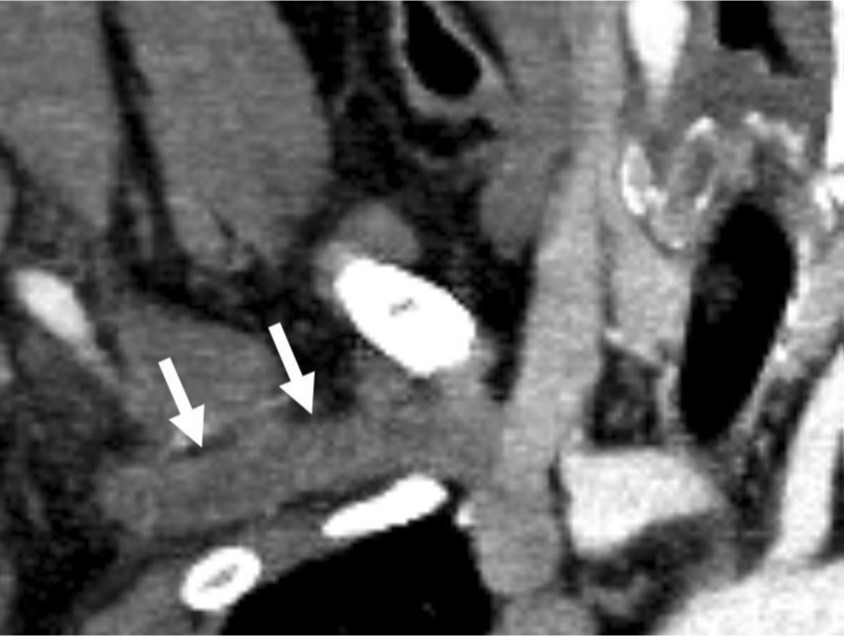

조영증강 CT에서 우측 쇄골하정 맥을 포함한 상지 심부정맥이 확장되어 있고 내부에는 혈전이 있었다(Fig. 1A-C). 우측 사각근간 삼각(interscalene triangle)에 의해 우측 쇄골하정맥이 명확하게 눌려진 소견은 없으며 우측늑쇄공간(costoclavicular space)도 좁아지거나 주변 구조물에 의해 눌려진 소견은 보이지 않아 반복적 인 작업에 의해 정맥이 눌린 노력혈전증( effort thrombosis)으로 생각하였다.

Fig. 1. A-C

Multiplan ar reconstructed images (A-C) shows contrast filling dtfecte (arrows) within right subclavian van.